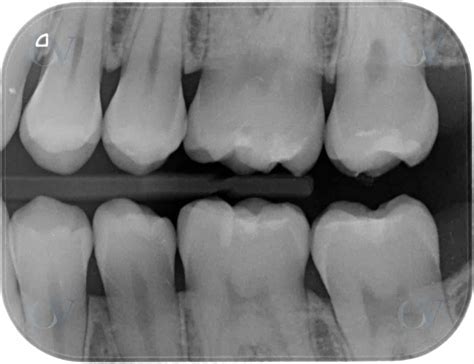

Las pruebas complementarias son una herramienta clave en el diagnóstico de la caries dental, siendo la principal la exploración radiológica. En la radiografía únicamente se aprecia el grado de mineralización dental, por lo que las zonas donde hay desmineralización se observan como radiolúcidas (oscuras) debido a los cambios en la absorción de los rayos X. Estas zonas radiolúcidas pueden indicar una lesión cariosa.

La radiografía de elección para el diagnóstico de la caries dental es la aleta de mordida, en la que se observa tres cuartos de los dientes, tanto superiores como inferiores, incluyendo tres dientes. Este tipo de radiografía intraoral es imprescindible cuando hay sospecha de caries interproximales.